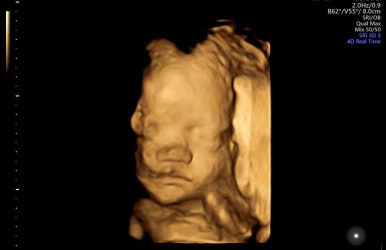

28주 1일

입체초음파로 태아의 얼굴을 볼 수 있는 시기이다!

제일 기다렸던 때이고, 다행히 태아 얼굴을 볼 수 있었다.